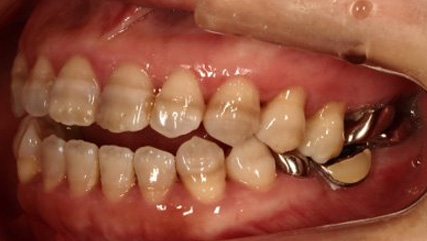

乱ぐい歯、でこぼこがとても酷い状態になります。歯が前後的に重なってしまっている、八重歯になっているなどがこのジャンルに入ります。

顎の大きさと歯の大きさのギャップが大きく、時には歯を抜かないと矯正治療ができない場合もあります。当院では治療期間が長くなるが抜かない治療方針など、一つの治療プランだけでなく、さまざまな可能性の治療方針を説明させて頂くよう心掛けております。こういった考え方はインフォームド・チョイスと言われ近年大切にされている考え方と言われております。

治療前

治療終了前